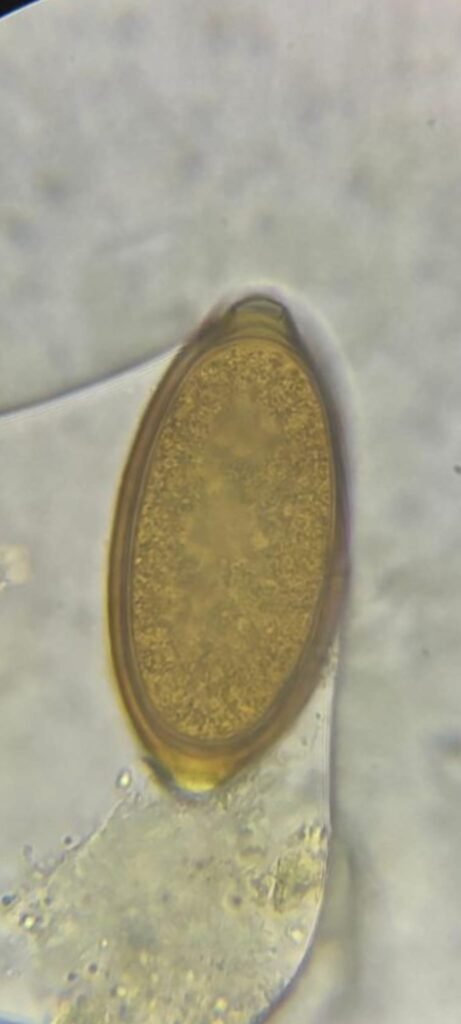

Analítica de heces

La analítica de heces o coprológico es una prueba sencilla pero muy útil para detectar parásitos intestinales como giardias, coccidios o lombrices, además de identificar alteraciones digestivas que pueden causar diarrea, pérdida de peso o malestar en tu mascota.

En nuestra clínica veterinaria en Vigo realizamos este test de forma rápida y no invasiva, tanto en revisiones rutinarias como cuando tu perro o gato presenta síntomas digestivos. Con los resultados podemos aplicar el tratamiento más adecuado y proteger la salud de toda la familia.